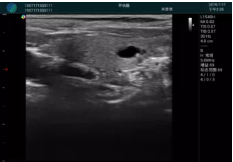

頸動(dòng)脈血流充盈飽滿(mǎn),無(wú)外溢

肝內血管顯示清晰,血流敏感無(wú)外溢

甲狀腺囊性結節,囊壁鈣化,透聲好

甲狀腺囊性占位